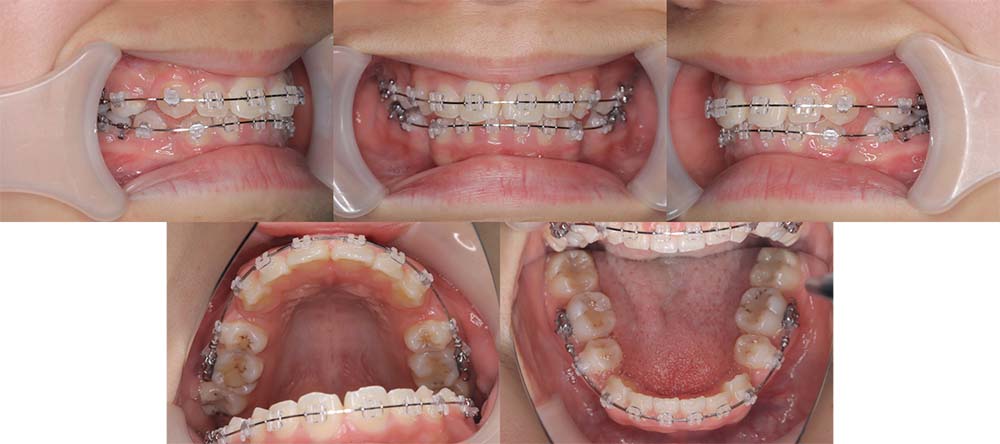

| 症例分類 | 上下顎前突、口唇突出 |

| 診断名 | 口唇突出を伴う上下軽度叢生 |

| 主訴 | 前歯が気になる |

| 年齢 | 15歳8ヶ月 |

| 性別 | 女性 |

| 抜歯部位 | 上下左右の第一小臼歯(4本) |

| 使用装置 | 表側のワイヤー装置 |

| 治療期間 | 1年9ヶ月 |

| 保定装置 | 固定式保定装置、取り外し式保定装置(8時間) |

| 費用 | [検査・診断料] ¥49,500 [基本施術料] ¥792,000 [調整料] ¥4,400/回 [抜歯] ¥5,500/本 [保定装置] ¥55,000(税込) 抜歯や虫歯治療は他院にて費用が別途かかります。(抜歯¥4,000〜10,000/本)

当初は前歯のガタガタを気にされており、上顎の部分治療を希望されました。しかしながら、上顎前歯の叢生のみの改善は可能だが、口唇突出感はなくなり、口が自然に閉じるようにするためには抜歯が必要なことを説明したところ、抜歯して治療することを希望されました。

上下第一小臼歯を抜去して表側のマルチブラケット装置で治療しました。顎間ゴムの協力度が良く予定より早く治療が終了することができました。

口唇突出感をなくし、しっかりと咬合することができました。